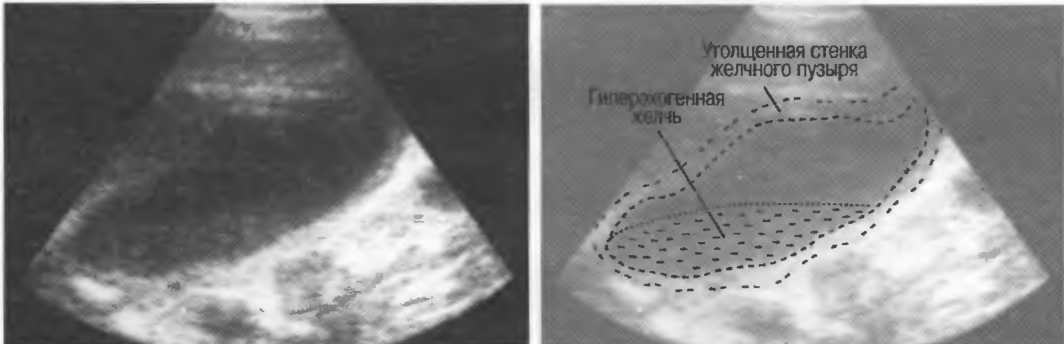

Взвесь(осадок) |

Эхогенная внутренняя структура различных размеров, формы, с неровным контуром в объемной структуре, содержащей жидкость. Может быть подвижной, изменяющейся при перемене положения тела пациента или при его движении. |

Ультразвуковые отражения от тканей с различным акустическим сопротивлением в одном органе. Внутренняя эхоструктура может, например, появляться в желчном пузыре при наличии конкрементов, взвеси в полости абсцесса. |

Гиперэхогенный (гиперэхоидный) |

Таким образом описываются ткани, создающие более яркие отраженные эхосигналы, чем рядом расположенные ткани, например кости, паранефральная клетчатка, стенка желчного пузыря, цирротическая печень (по сравнению с нормальной печенью). |